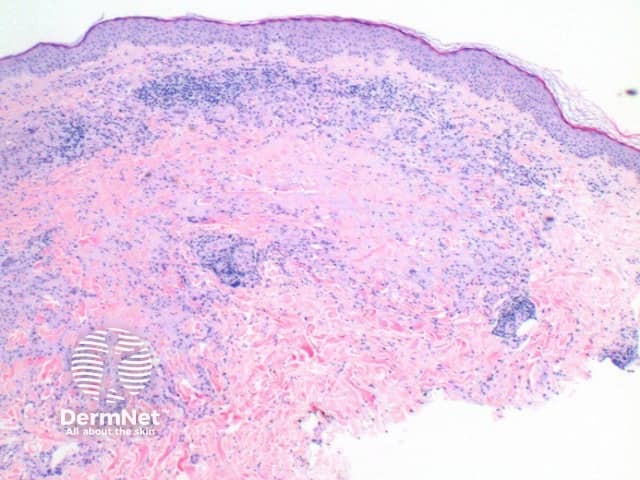

The scanning view of the histology of granuloma annulare shows a granulomatous inflammatory pattern situated within the superficial and mid dermis.

Figure 1